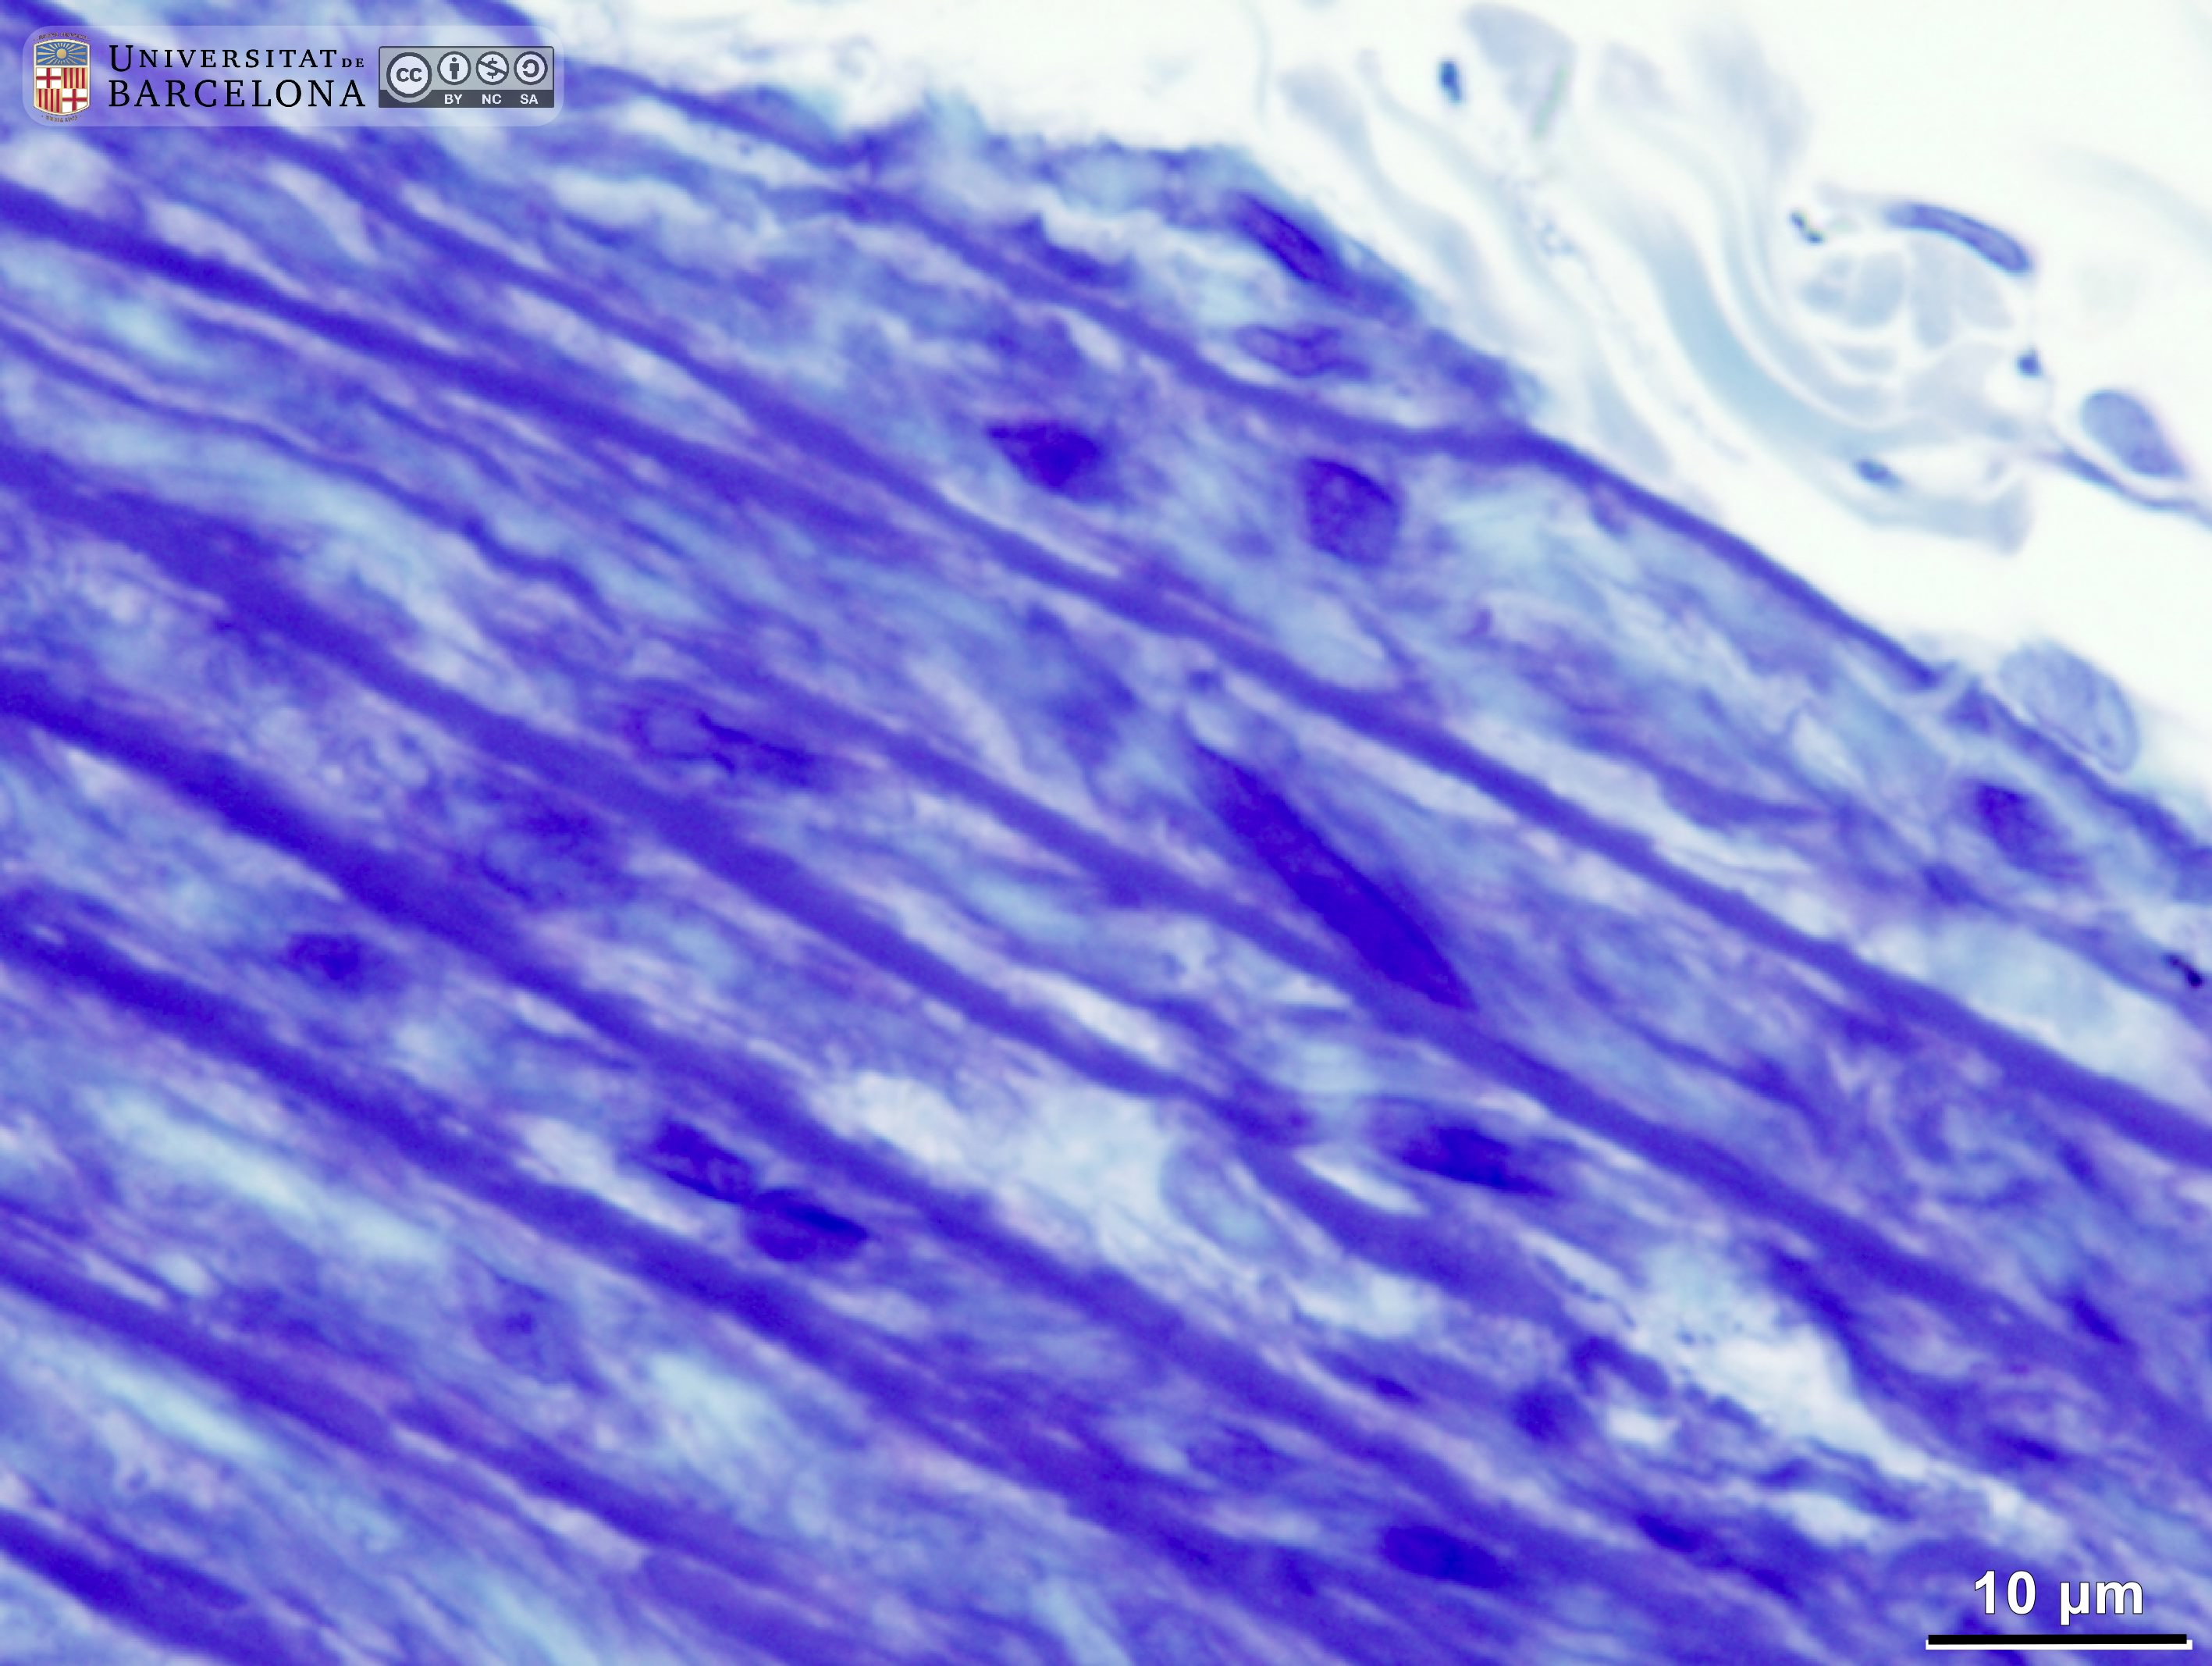

Blood vessels: aorta

[ENG] Collection of micrographs on the organisation of the arterial wall in the aorta -thoracic and abdominal- in paraffin sections and epoxy, semithin sections. Samples from rats and other species. The three tunicae -intima, media and adventitia- are shown, including the layered pattern of elastic fibres in the tunica media. [CAT] Col·lecció de micrografies de l'organització de la paret de l'aorta (toràcica i abdominal) en talls de parafina i talls semifins de resina epoxy. Mostres de rata i altres espècies. Es mostren les tres túniques (íntima, mitjana i adventícia) amb la laminació característica de les fibres elàstiques en la túnica mitjana.